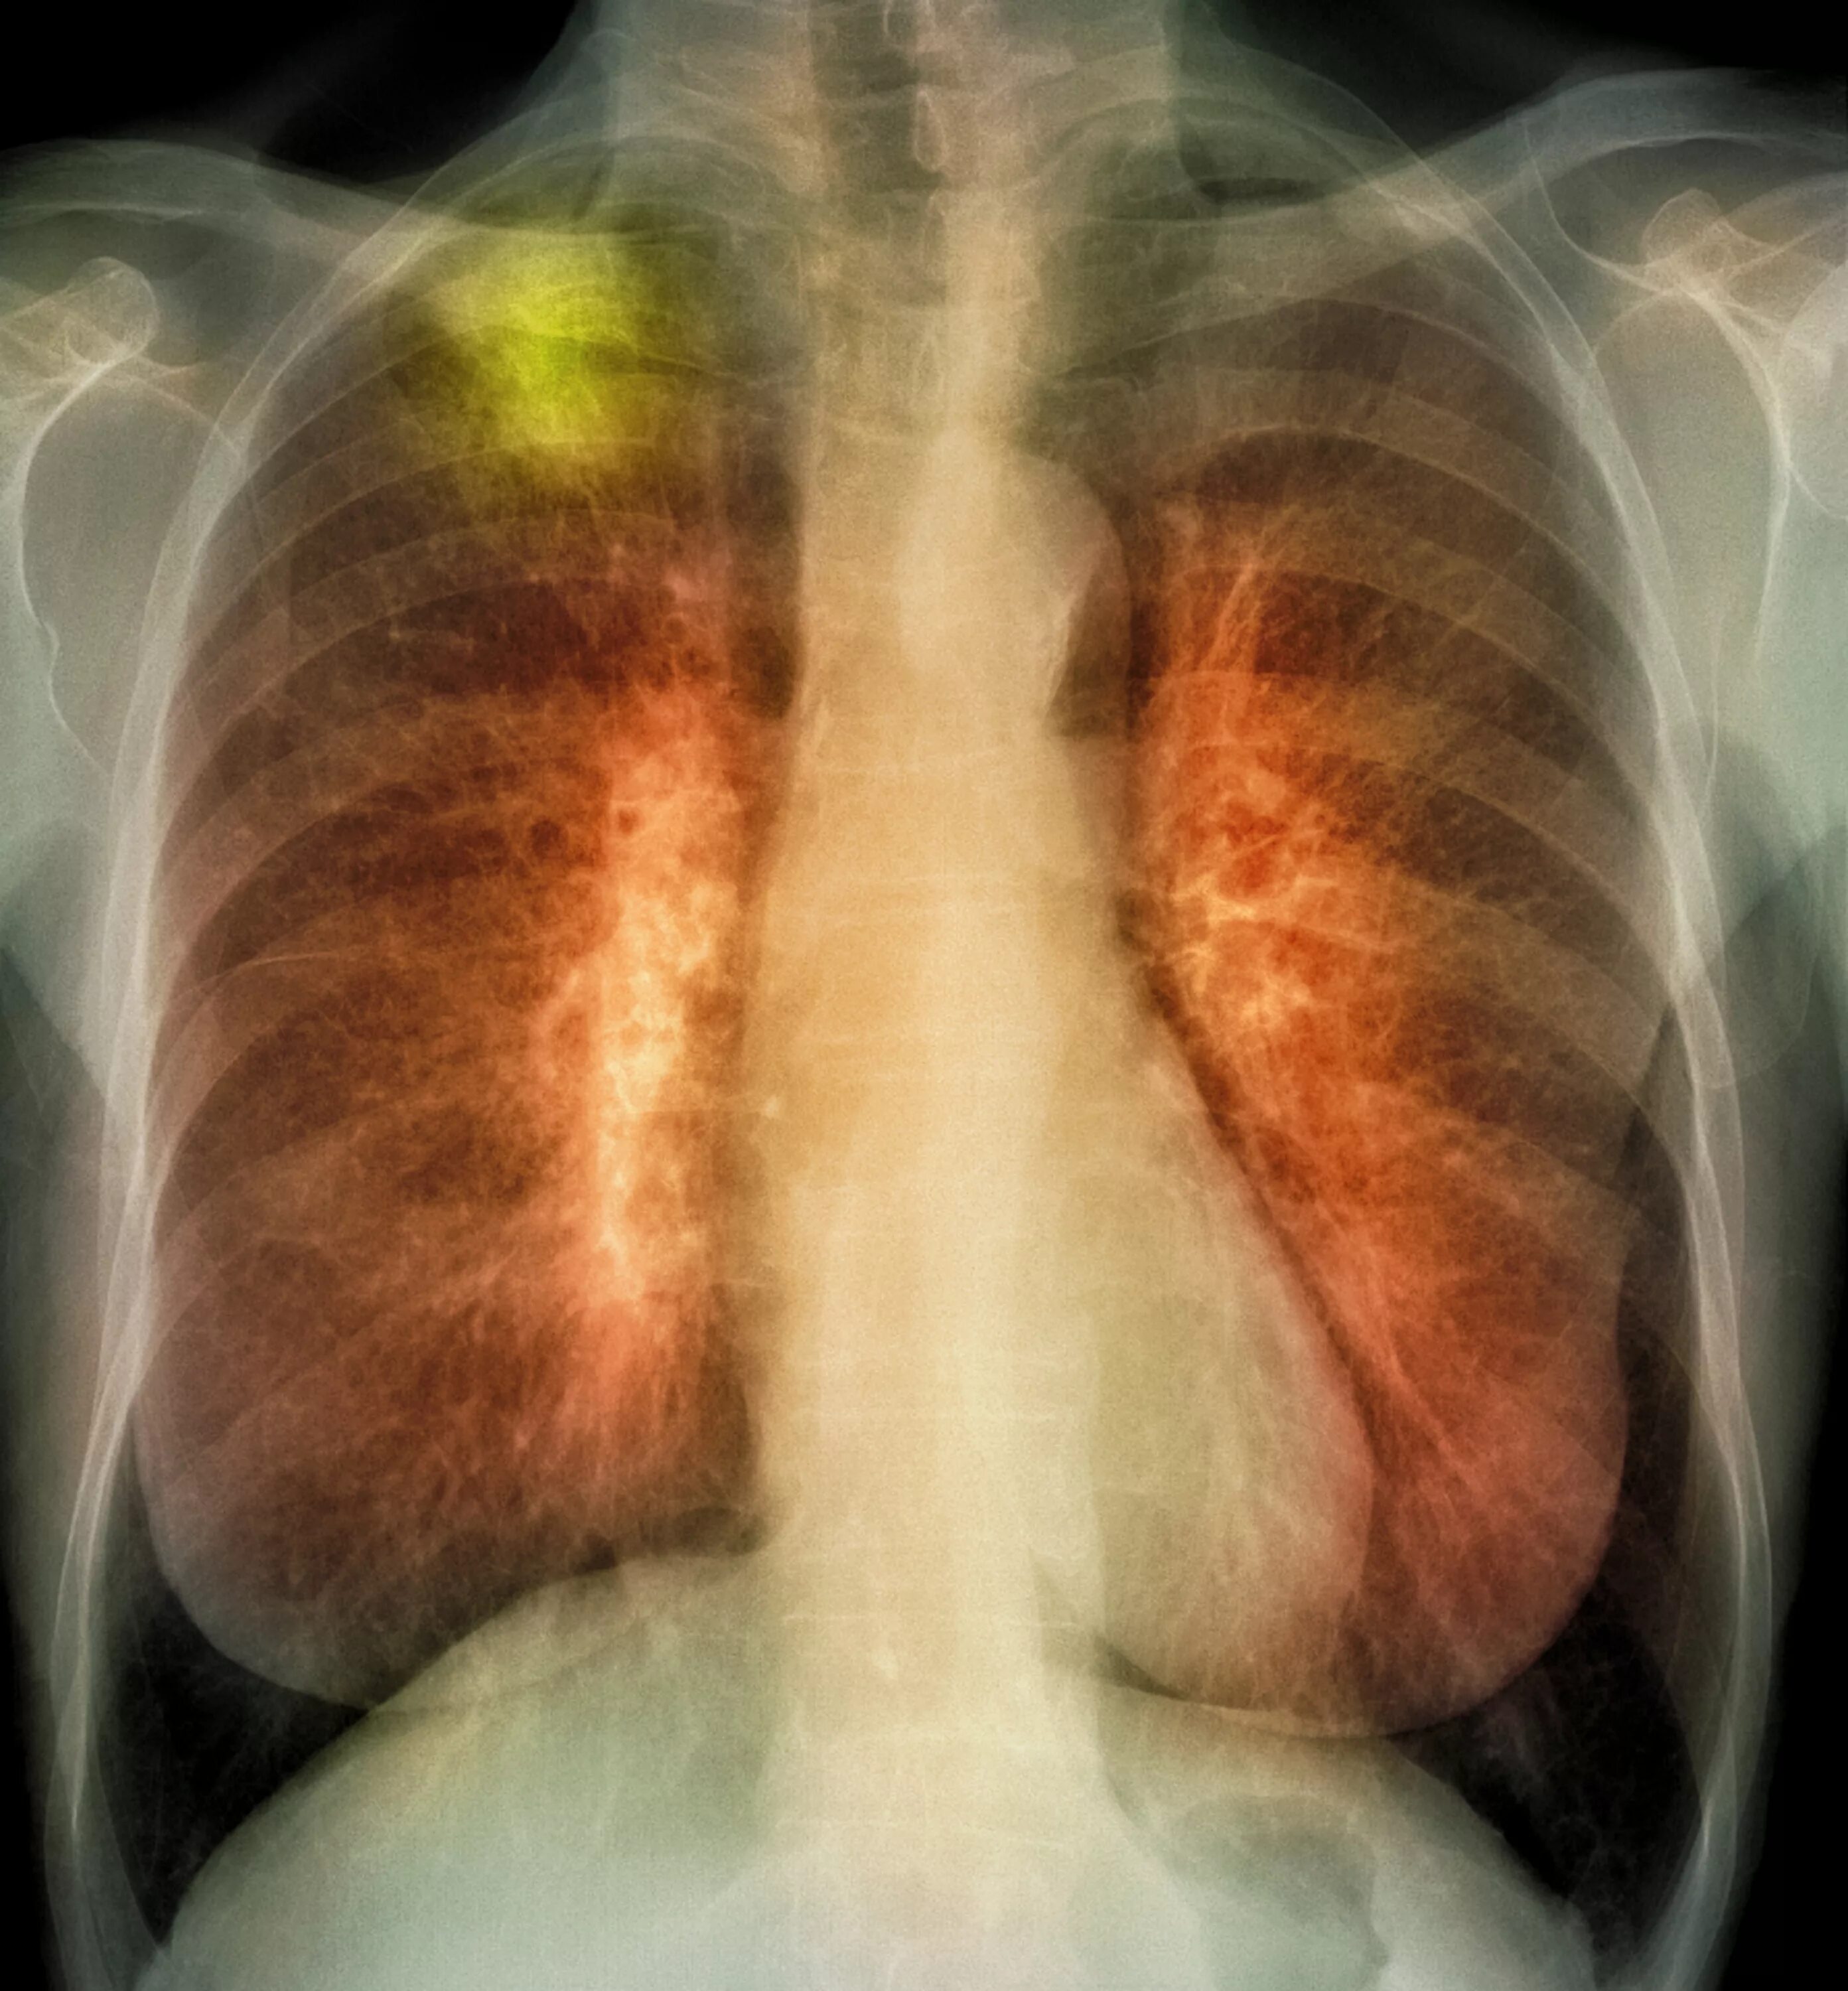

Онко легкие